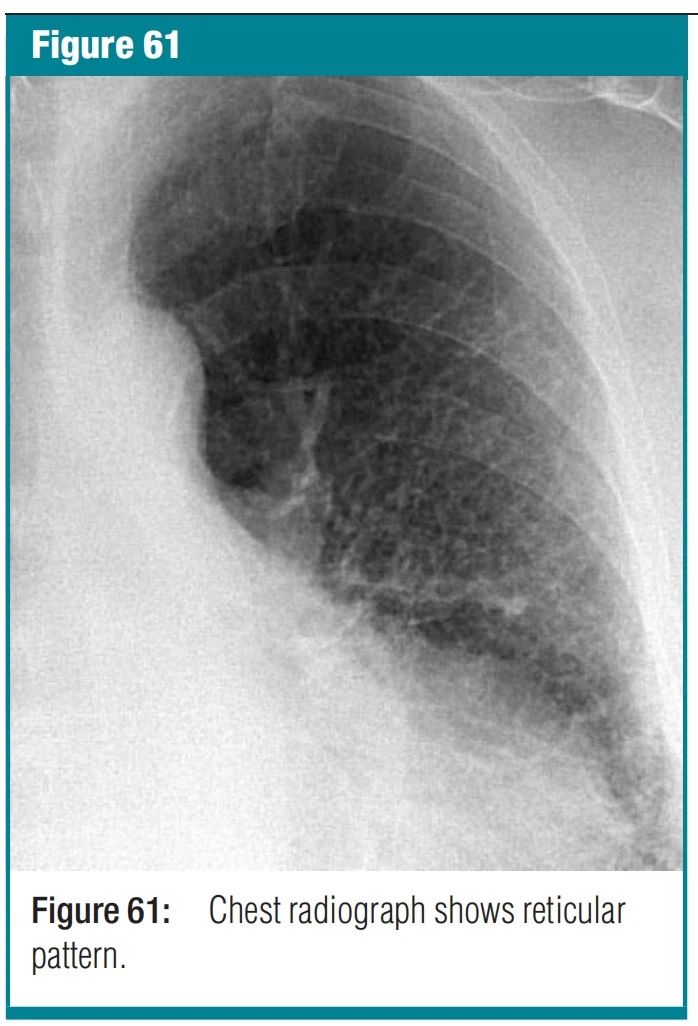

图10 reticulonodular pattern-网状结节影是网状影和结节影重叠在一起。本征象常是大量线状影相互交叉时形成的小结节影。结节的大小和数量取决于线状影的大小和数量。在CT图像上,本征象表现为网状影和结节影同时出现。小结节可以位于网状影的中央(例如小叶中心性小结节),或者线样密度影上的结节(间隔结节)。